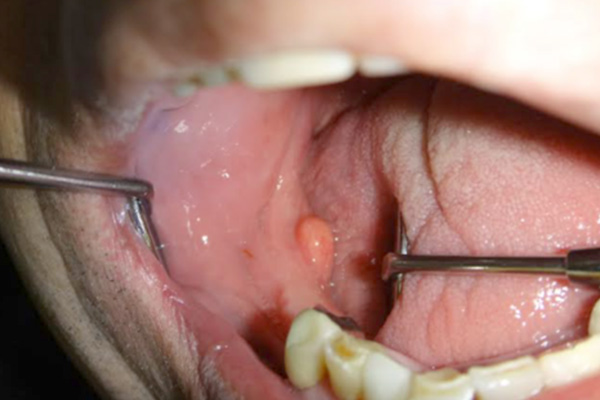

粘液嚢胞

唾液の流出障害によって起こる嚢胞です。自然消退することもありますが、何度も繰り返す際は切除を検討します。主に下唇や舌下部に発症します。